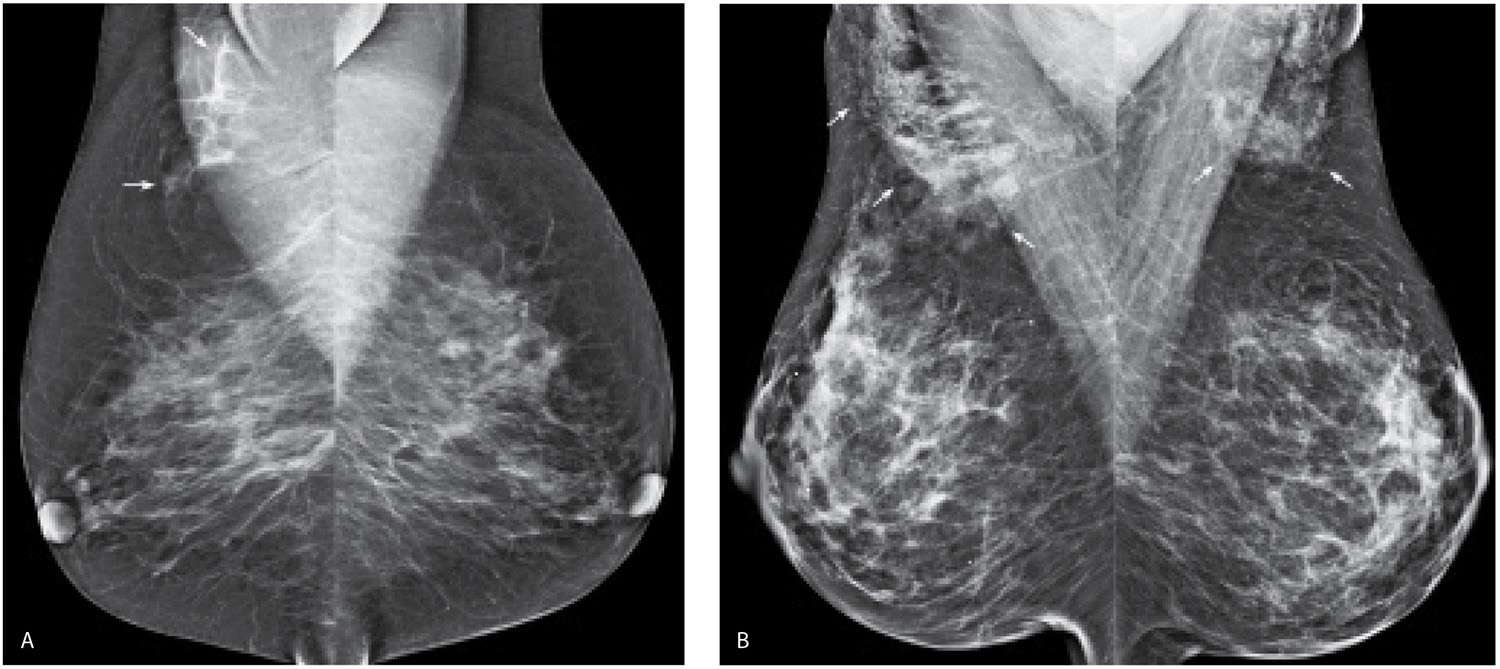

Miscellaneous Mammographic Findings Radiology Key What Is Accessory Axillary Breast Tissue 1 it is found in up to 6% of the population with the highest incidence in japanese. Accessory breast tissue is defined as “residual [breast] tissue that persists from normal embryologic. For example, near your armpits. Accessory breast tissue is residual breast tissue that results from failure of regression during embryogenesis. Breast tissue is responsible for the shape and size. What Is Accessory Axillary Breast Tissue.

The ABCs of Accessory Breast Tissue Basic Information Every Radiologist Should Know AJR What Is Accessory Axillary Breast Tissue Breast tissue is responsible for the shape and size of your breasts. 1 it is found in up to 6% of the population with the highest incidence in japanese. Axillary breast tissue, or accessory breast, is excessive breast glandular and fat tissue that accumulates in and around the axilla. Accessory breast tissue is defined as “residual [breast] tissue that persists. What Is Accessory Axillary Breast Tissue.

The ABCs of Accessory Breast Tissue Basic Information Every Radiologist Should Know AJR What Is Accessory Axillary Breast Tissue Breast tissue is responsible for the shape and size of your breasts. However, the tissue can sometimes develop beyond the breasts themselves. 1 it is found in up to 6% of the population with the highest incidence in japanese. Accessory breast tissue is residual breast tissue that results from failure of regression during embryogenesis. For example, near your armpits. Accessory. What Is Accessory Axillary Breast Tissue.

The ABCs of Accessory Breast Tissue Basic Information Every Radiologist Should Know AJR What Is Accessory Axillary Breast Tissue Accessory breast tissue is residual breast tissue that results from failure of regression during embryogenesis. 1 it is found in up to 6% of the population with the highest incidence in japanese. Axillary breast tissue, or accessory breast, is excessive breast glandular and fat tissue that accumulates in and around the axilla. Accessory breast tissue, residual breast tissue persisting from. What Is Accessory Axillary Breast Tissue.

The ABCs of Accessory Breast Tissue Basic Information Every Radiologist Should Know AJR What Is Accessory Axillary Breast Tissue Accessory breast tissue is residual breast tissue that results from failure of regression during embryogenesis. For example, near your armpits. Accessory breast tissue, residual breast tissue persisting from embryologic development, is found in up to 6% of the population, most. Accessory breast tissue is defined as “residual [breast] tissue that persists from normal embryologic. However, the tissue can sometimes develop. What Is Accessory Axillary Breast Tissue.